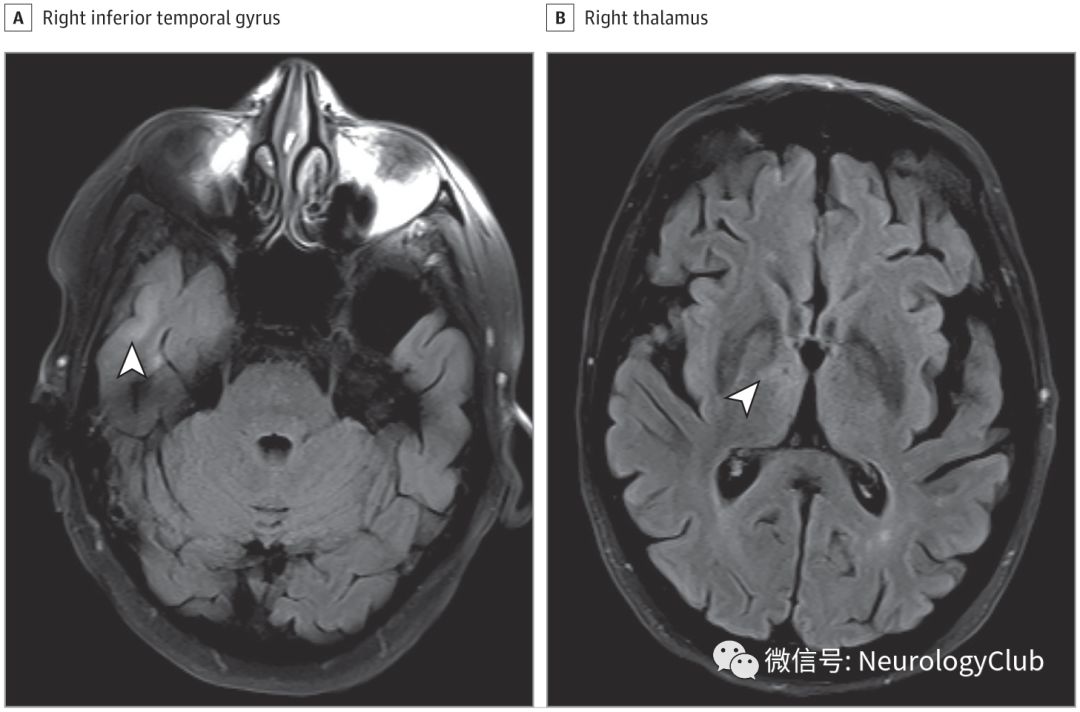

患者头颅增强MRI正常。乙酰胆碱受体抗体和肌肉特异性激酶抗体检测阴性。重复电刺激和单纤维肌电图无殊,也没有周围神经病变的证据。促甲状腺素,硫胺素水平,莱姆病抗体,快速血浆反应素和血清神经节苷脂抗体检测均无殊。脑脊液化验提示有核细胞数6/μL(转换为×10^9/L,乘以0.001),淋巴细胞占88%,红细胞计数10/μL,蛋白水平0.087g/dL(转换为g/L,乘以10),葡萄糖水平63mg/dL(转换为mmol/L,乘以0.0555)。血清副肿瘤抗体(抗VGKCC,电压门控钙通道,Hu,Ri,Yo,amphiphysin)检测结果均为阴性。3周后复查头颅MRI可见右侧丘脑,颞下回和海马T2/FLAIR高信号(图)。

(图:患者起病3周后复查头颅MRI,FLAIR可见右侧颞下回和右侧丘脑高信号)